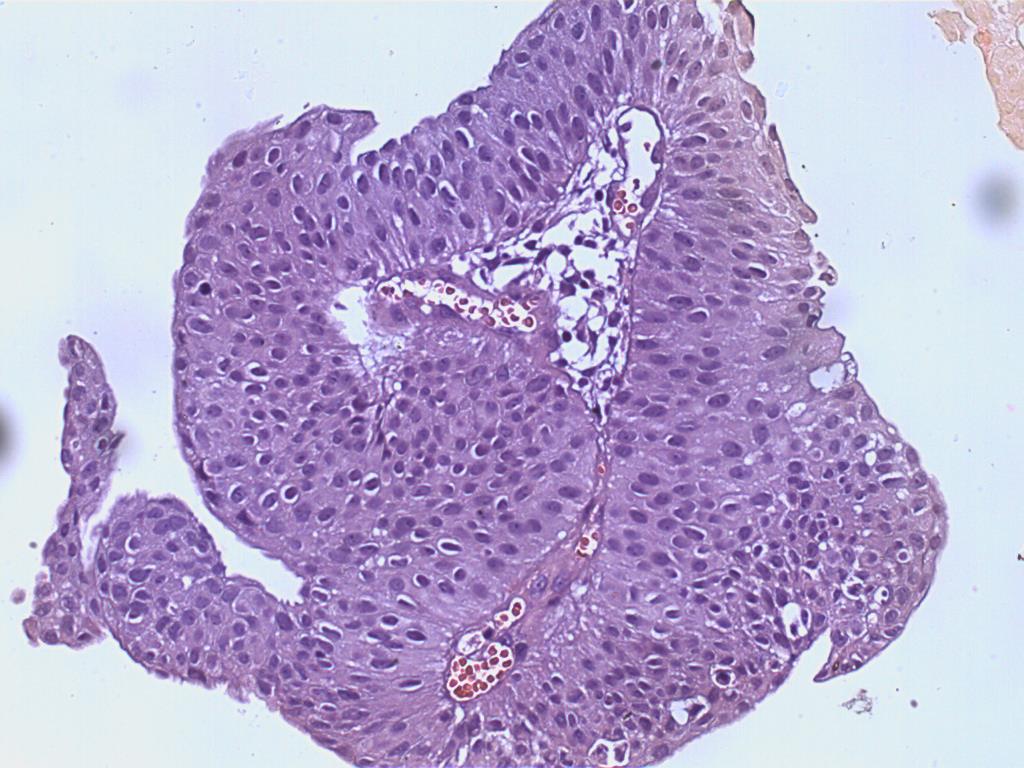

Bladder Papillary Lesions

Case ID: 487